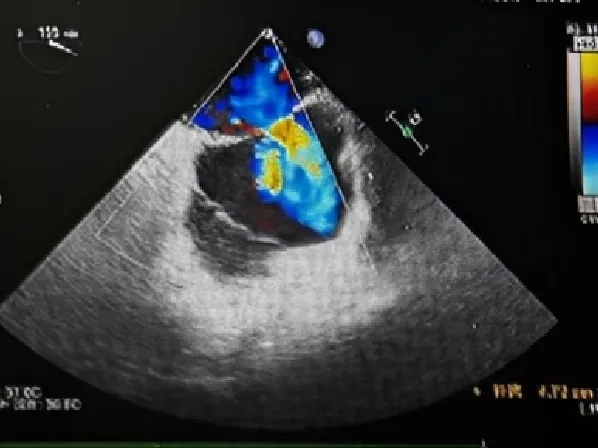

经食道超声描述:四腔心切面观:房间隔总长约48mm,中部卵圆窝处菲薄。房间隔中部回声中断约12.6mm,残端距二尖瓣环约23mm(软缘,房间隔中部菲薄),距房顶部约13mm(硬缘)。双腔切面观:房间隔中部回声中断约14.6mm,残端距上腔静脉约15.8mm(硬缘),距下腔静脉约23.8mm(硬缘)。大动脉短轴切面观:房间隔回声中断约12mm,主动脉侧几乎无残端,距心房侧约18mm(硬缘)。CDFI: 房水平可见左向右分流血流信号。三尖瓣口见少量反流血流信号。

超声提示:继发孔型房间隔缺损,房水平左向右分流。